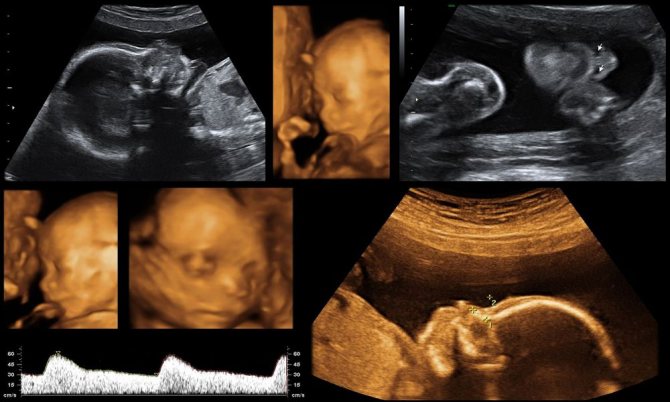

- ультразвуковое исследование;

Заподозрить выкидыш можно по внезапным кровянистым выделениям и резкой боли внизу живота. При появлении этих симптомов следует срочно обратиться за медицинской помощью. Врач должен провести УЗ-диагностику. Золотым стандартом диагностики считается трансвагинальной сканирование (ТВС) — когда датчик вводится в матку через влагалище. Если ТВС недоступно, можно применить трансабдоминальное сканирование — через переднюю брюшную стенку.

Замершая беременность может протекать бессимптомно и не проявляться вплоть до очередного планового УЗИ.